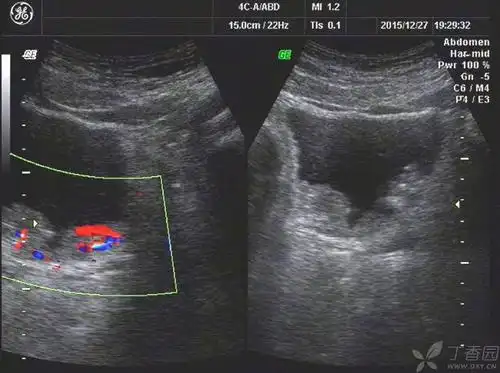

膀胱平滑肌瘤是一种来源于膀胱壁平滑肌组织的非上皮性良性肿瘤可

典型的膀胱癌一例

膀胱占位

膀胱肿瘤

(膀胱癌)

膀胱癌的超声影像诊断分析

【请教】膀胱癌?